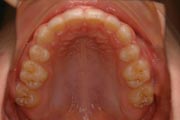

Crowding

After